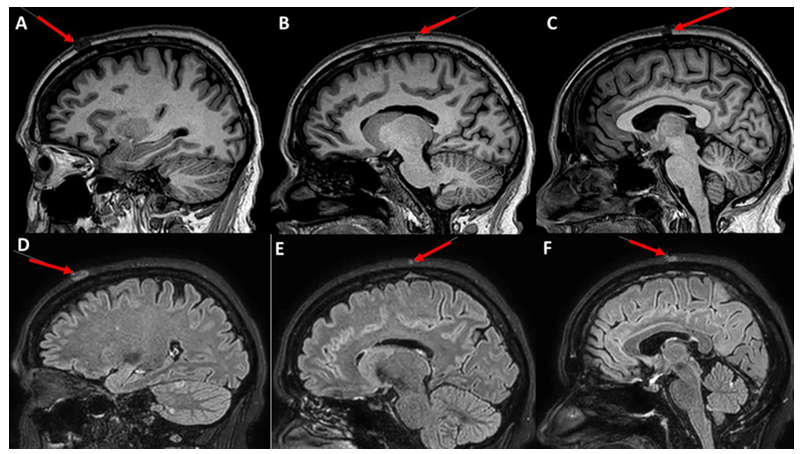

图片2.png

脑部磁共振成像(MRI)进一步证实了头皮病变的存在。在T1加权非造影序列上,病灶表现为低信号(Hypointense);而在液体衰减反转恢复序列(FLAIR)增强后图像上,病灶则呈现高信号(Hyperintense)。影像学特征明确提示了软组织结节的性质,支持了转移性病变的诊断假设。